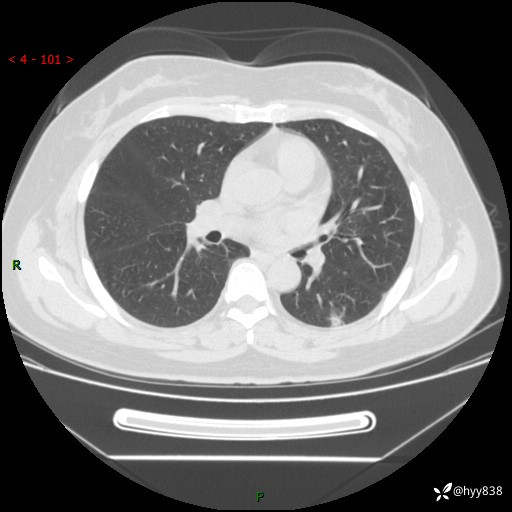

胸部CT平扫(2023.3)